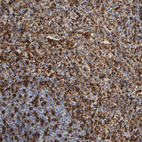

Immunohistochemical staining of human spleen shows strong cytoplasmic positivity in cells in red pulp and in subset of cells in white pulp.